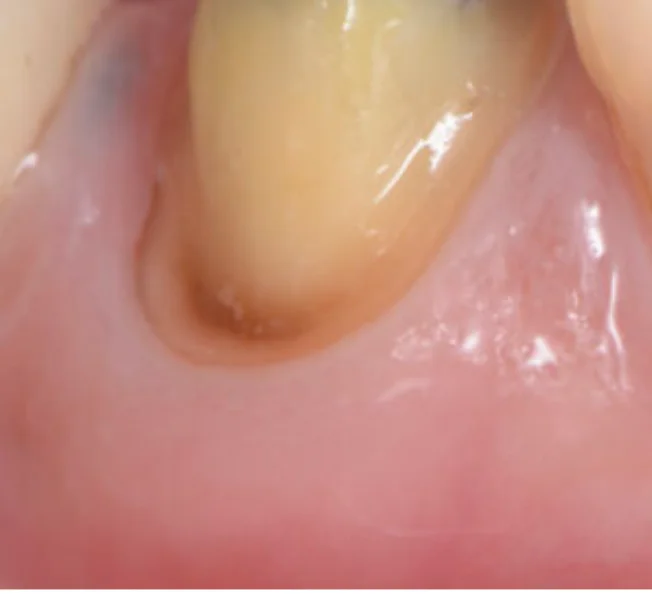

Before

After

セラミック治療により見た目と歯茎の炎症を改善(40代女性)

5回 / 総額115,000円リスク・副作用:歯軋りが強い場合破損する場合がある 歯の神経が生きている場合一時的にしみることがある